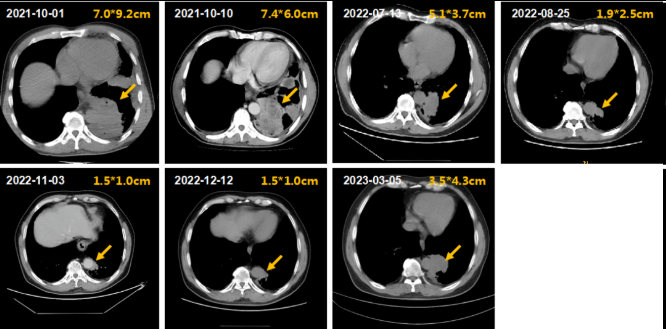

③胸部靶病灶的影像学(CT)变化:患者左下肺占位初治时大小为7.0cm*9.2cm,给予IP/IC方案化疗后逐渐缩小至1.5cm*1.0cm,接着给于同步放化疗,靶病灶未见明显缩小或增大。2023年3月5日复查胸部CT提示左肺下叶斑片状高密度影,大小约3.5cm*4.3cm,邻近支气管狭窄;右肺中叶小结节,直径约3mm,随诊;双肺散在纤维灶;双侧胸膜增厚;胸椎骨质增生(图2)。

图2.患者肺部靶病灶的CT改变